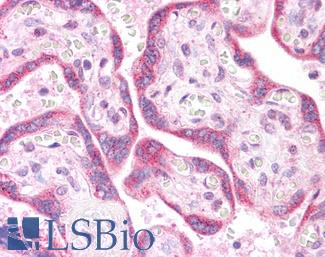

CK14 (KRT14)

Anti-KRT14 / Cytokeratin 14 antibody IHC of human skin. Immunohistochemistry of formalin-fixed, paraffin-embedded tissue after heat-induced antigen retrieval. Antibody LS-B3916 dilution 1:25.